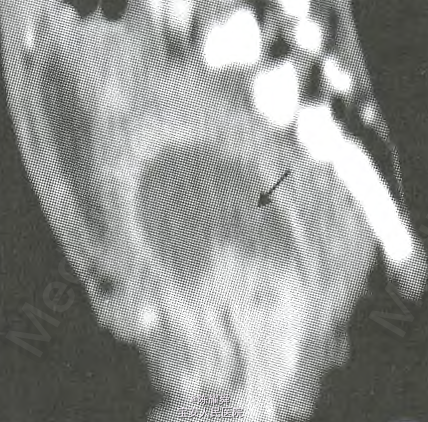

查体:会阴部流出暗红色血流,量多,腹软,无压痛、反跳痛,未及明显包块。 盆腔增强CT诊断:直肠前间隙内示不规则团块状囊实性异常强化灶.大小约3.7cm×3.2cm,直肠前间隙囊实性占位,恶性肿瘤可能大。

临床诊断:阴道卵黄囊瘤。 处理:行盆腔肿物切除术,术中探及肿瘤源于阴道经后穹窿突入盆腔,瘤体浸润整个阴道,与部分直肠前壁严重粘连。切取部分肿瘤组织送常规病检。术后病理诊断:阴道卵黄囊瘤。